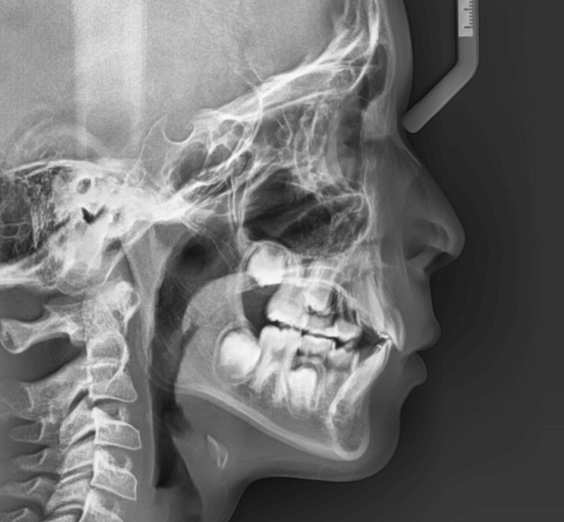

上歯前突+叢生症例 成長期

主訴 | 口元の突出感と歯並びが気になり、将来的な咬合状態を整える目的で来院された患者様です。 |

---|---|

診断結果 | 11歳1か月の女性。骨格的には日本人標準に近く、歯性の上顎前突および叢生が認められました。上下顎ともに歯列のスペース不足があり、永久歯の萌出や歯列の整列に支障をきたす可能性があると診断されました。 |

治療内容 |

|

治療後の経過 | 動的治療終了後は、上下顎の歯列が整い、口元の突出感と叢生が改善されました。審美的・機能的なバランスが取れた状態となり、現在は取り外し式リテーナーを使用し、保定期間に移行しています。 |

治療期間 | 動的治療期間:2年6か月 通院回数:25回 |

治療費用 | 720,000円 |